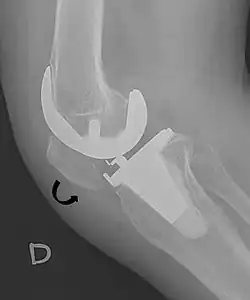

A patella baja is a low-riding patella. A long-standing patella baja may result in extensor dysfunction.[6]

The Insall-Salvati ratio helps to indicate patella baja on lateral X-rays, and is calculated as the patellar tendon length divided by the patellar bone length. An Insall-Salvati ratio of < 0.8 indicates patella baja.[7]

- ^ a b Douglas Dennis (2017-02-25). "TKA in Patella Baja (Infera)". Orthobullets. Retrieved 2019-02-08.